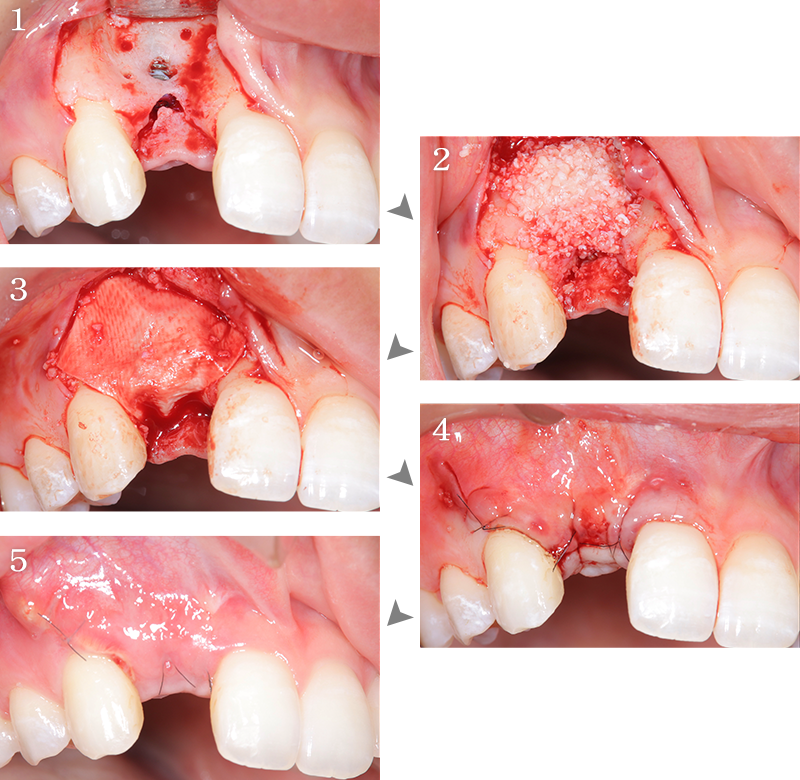

CASE1

右上前歯部にGBRを併用しインプラント治療を行なった1症例

主訴 右上の前歯に歯を入れたい

治療内容 右上側切歯インプラント、GBR

治療期間 約1年

費用 インプラント埋入手術:27.5万円(税込)

セラミック補綴:22万円(税込)

GBR:11万円(税込)